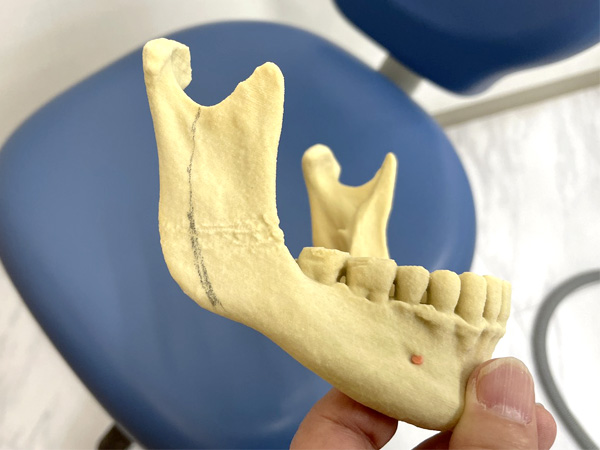

下顎枝垂直骨切り術(IVRO)の

骨切りデザイン

① IVROの

② IVROの

骨切り

③ IVROの骨切り結果と

干渉部分のチェック

④ IVROの骨切り結果と

可動時の干渉部分のチェック

CBCTやパノラマレントゲンをもとに、移動する下顎の予定位置や骨切りラインの神経、血管の走行に留意してデザインをおこなう。